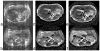

With the development of numerous mouse models of cancer, there is a tremendous need for an appropriate imaging technique to study the disease evolution. High-field T(2)-weighted imaging using PROPELLER (Periodically Rotated Overlapping ParallEL Lines with Enhanced Reconstruction) MRI meets this need. The two-shot PROPELLER technique presented here provides (a) high spatial resolution, (b) high contrast resolution, and (c) rapid and noninvasive imaging, which enables high-throughput, longitudinal studies in free-breathing mice. Unique data collection and reconstruction makes this method robust against motion artifacts. The two-shot modification introduced here retains more high-frequency information and provides higher signal-to-noise ratio than conventional single-shot PROPELLER, making this sequence feasible at high fields, where signal loss is rapid. Results are shown in a liver metastases model to demonstrate the utility of this technique in one of the more challenging regions of the mouse, which is the abdomen.